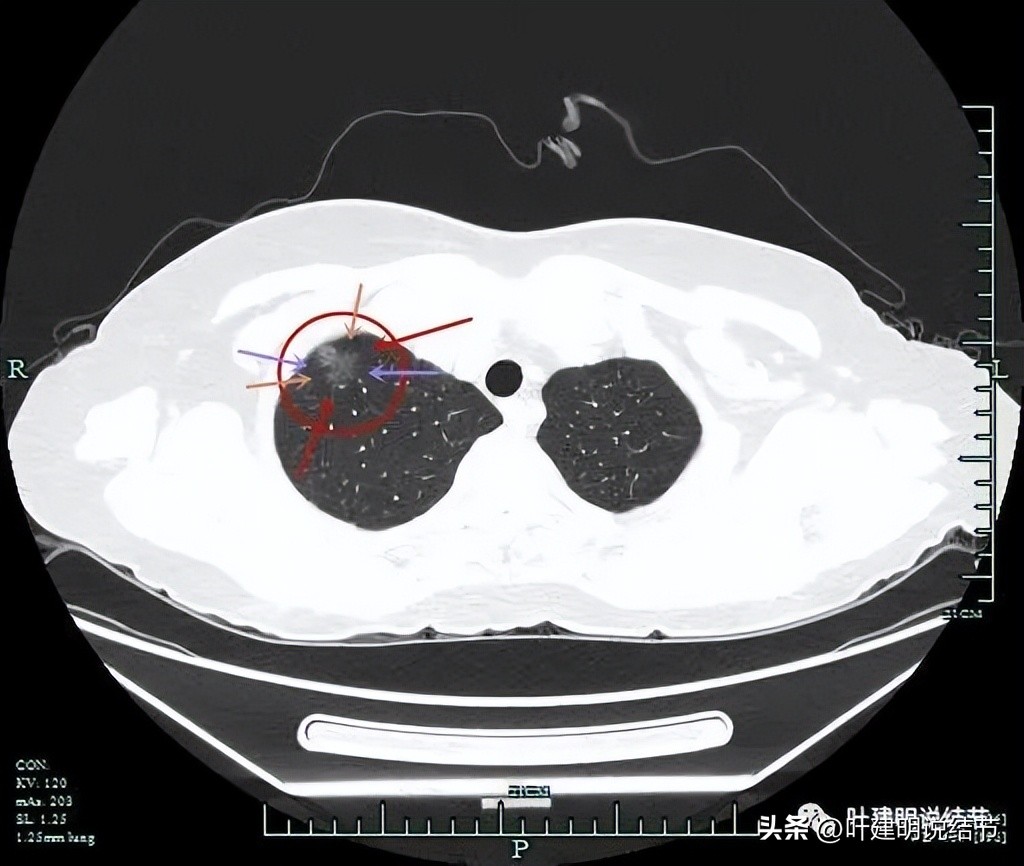

血管进入,间隙消失、轮廓清

上图也非常典型,几乎集齐它该有影像特征:灶内实性成分(粉色箭头);与胸壁间间隙消失(蓝色箭头);整体轮廓与瘤肺边界清(红色箭头);灶内血管穿行以及小血管进入(桔色箭头);表面不平有分叶(砖色箭头);边缘有毛刺征(紫色箭头)。

这是非常典型的表现为混合磨玻璃的浸润性腺癌。炎性的病灶瘤肺边界不会这么清楚的,微浸润性腺癌不会有这么明显的实性成分的。当然比这种病灶还要典型的则是实性成分再多些,并有纠集感,边缘毛刺再长点并有锐利感,分叶再深点并有膨胀感。